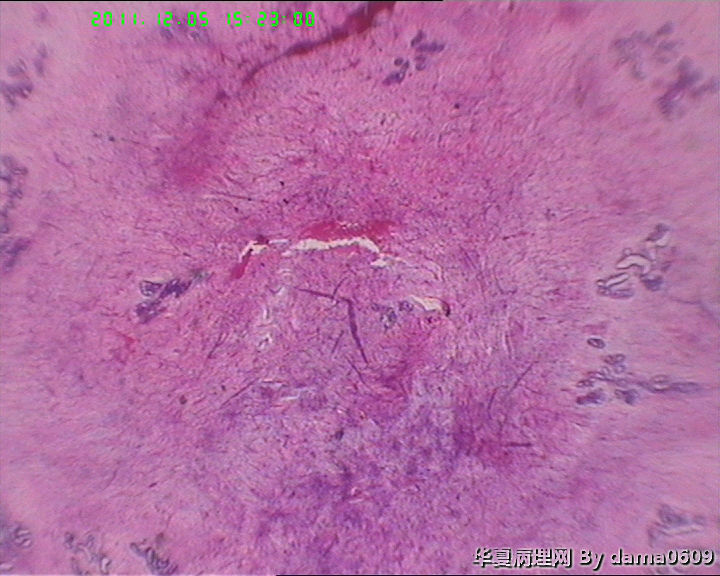

肿物一:镜下见乳腺小叶结构紊乱,小叶内、小叶间间质增生,构成肿瘤主质。增生间质呈梭形细胞样,细胞稀疏、异性不明显,其间见大量胶原纤维,小血管增生,局灶有红细胞渗出。见到一处导管大汗腺化生。

肿物二:镜下呈结节状,结节以导管或小叶为中心,围以增生的间质成分,梭形细胞构成,稀疏,增生的血管呈“鹿角状”。大结节内见局灶间质有出血或红细胞外渗,局灶导管内间质增生呈乳头/分叶状,上皮下无密集增生的间质细胞。结节大小不等,以窄带样纤维细胞束彼此分隔,互不融合,纤维细胞束细胞密集,内有增生的小血管。